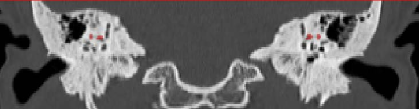

Annotation of the lateral semicircular canal plays an important role in the automatic calibration method of the raw temporal bone CT image. However, large-scale medical image data annotation is expensive and difficult to obtain. Therefore, we proposed an LSC segmentation algorithm to roughly predict the location of anchors. The lateral semicircular canal is a small sophisticated anatomical structure in the temporal bone. It is a semicircle canal that embedded in the temporal bone. In a CT volume, a lateral semicircular canal contains about 200 to 300 voxels. In different observation positions, the LSC vary greatly, as shown in Figure 2, which also makes it difficult to segment accurately.

Refer to caption

(a) Transverse position

(b) Coronal position

(c) Sagittal position

Figure 2: The LSCs in different views.